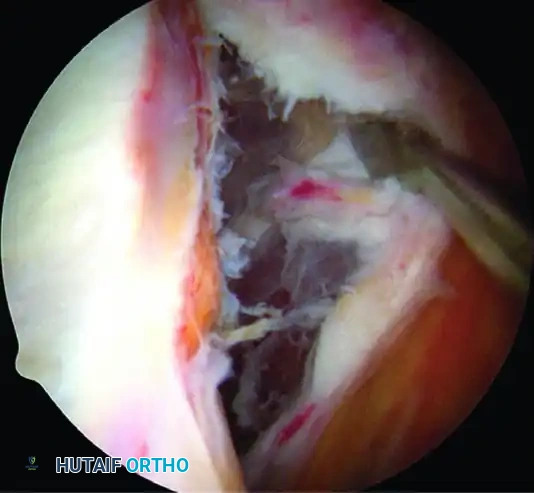

3. Anterior Anchor Placement

Transition to the anterior Bankart repair. The goal is to secure anatomical fixation 2 mm onto the articular surface with a minimum of three (preferably four) suture anchors, spaced 5 to 7 mm apart.

A, Capsule and labral complex freed.

The Inferior Anchor (The Keystone):

The most critical anchor is the most inferior one. Use the 5-o’clock percutaneous portal with a spinal needle for precise trajectory (45-degree angle to the articular surface). Place the spear guide at the 5:30 position, 1 to 2 mm onto the articular cartilage margin. Drill and insert a biocomposite or all-suture anchor (e.g., JuggerKnot).

B, Anchor inserted on articular edge.

4. Suture Passing and Superior Advancement

To eliminate the drive-through sign and restore physiological tension, the capsule must be shifted superiorly and laterally.

- Retrieve the most inferior suture limb out of the posteroinferior cannula using a suture grasper.

- Use a Spectrum suture passer through the anterior cannula to take a substantial (1 cm) bite of the capsule and labrum inferior to the anchor site.

C, A 1-cm capsular bite taken with Spectrum suture passed distal to anchor.

- Shuttle the PDS relay suture out the posterior cannula, load the anchor suture, and pull it through the capsulolabral tissue.

- Retrieve the corresponding suture limb and tie a secure, low-profile sliding knot (e.g., SMC or Weston knot) backed up by alternating half-hitches.